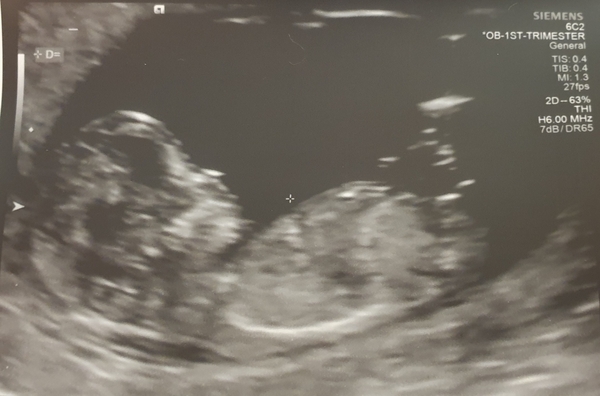

Anywhoo here's my pic everything seems to be ticking along nicely, so happy to get a pic, finally feels so real xxx new due date for me is 23rd May. _

@PrinnyPree another great scan pic!!

@PrinnyPree Lovely pic!! Baby looks so cosy!!

@sao81 Not had any bleeding myself and this is my first, but have seen plenty of Mums on the forum who've had bleeds and everything is perfectly fine, sending loves as it must be worrying. Love the pic of your little wriggler _ xxx

@sao81 Lovely scan pic, glad everything is ok!